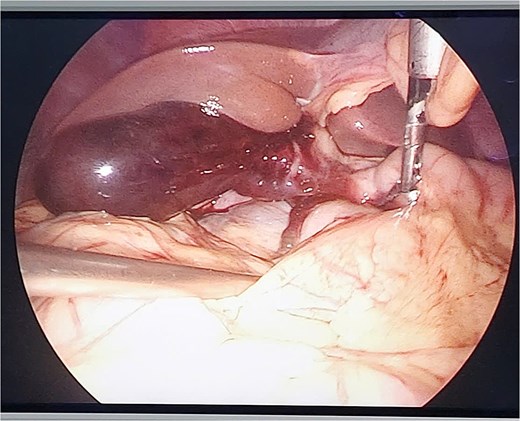

The patient was indicated for diagnostic laparoscopy. During laparoscopic surgery, gallbladder contusion was found and there was a presence of free blood in the peritoneal cavity, but no hollow organ rupture was observed (Fig. 2).

Conversion to open surgery was continuously done to examine the entire duodenum and digestive tract. We explored the omental bursa and then performed Kocher and Cattell-Braasch maneuvers, with any injuries being observed. A cholecystectomy was then performed, followed by cavity lavage with saline, and primary abdominal fascial closure, with abdominal drainage. The patient recovered without complications on the 6 postoperative day and was continuously transferred to The Orthopedic and Trauma Center for broken bone surgery (Fig. 3).